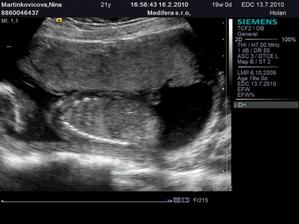

♥ 16.2. (utorok) ideme na 4D ultrazvuk!! 🙂 - Boli sme, nádherný zážitok!!! Je to chlapec ako sa patrí, úplne zdravý a krásny!!! 🙂 4D nám lekár ukázal len nožičky a pipíka, lebo tvárička nie je dobre vidieť tak skoro, ale to vôbec nevadí... 🙂